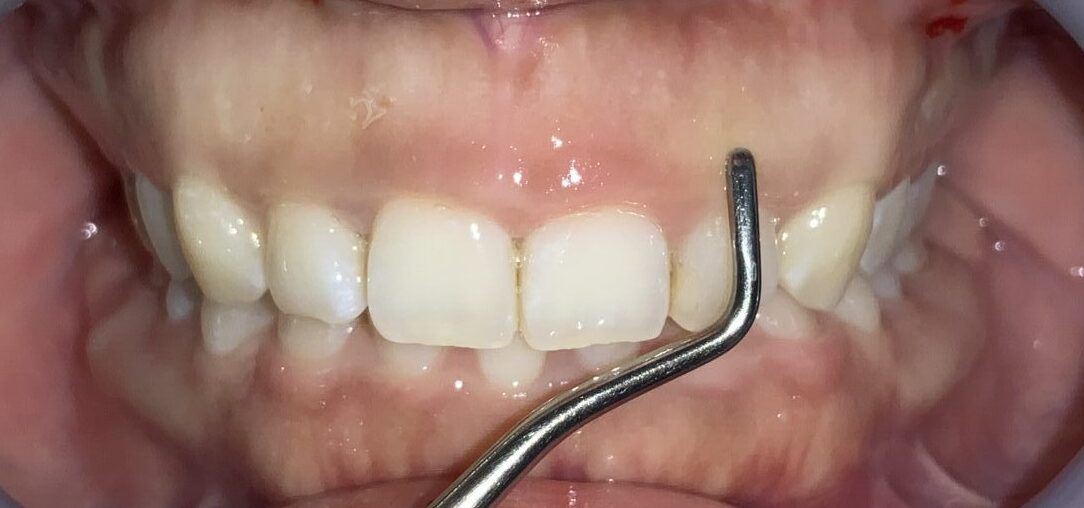

この歯は犬歯です。犬歯もたくさんの歯ぐきに覆われているようですが、治療をする場合には注意が必要です。

犬歯はあまり大きくすると、八重歯のように見えてしまい、せっかくの治療が台無しになる場合があります。また、被っている歯ぐきがたくさんあっても、歯ぐきが薄い場合があり、このような歯ぐきの場合は、治療後に歯ぐきが退縮してしまい、歯槽膿漏の歯ぐきのように見えてしまう場合があります。

難関の犬歯を超えたところで、第一小臼歯の4番面の歯を検査します。

奥歯なのに、歯ぐきがたくさん被っているようです。3番目の犬歯と違い、奥歯の形になってきている4番目の歯は、犬歯とは違う注意が必要です。

この歯は奥歯の形なので、歯ぐきを取りすぎると、知覚過敏になる場合があります。また、前歯と奥歯の間の歯ですから、前歯に比べて治りが遅い傾向にあります。歯ぐきの切除も慎重に行わなければなりません。